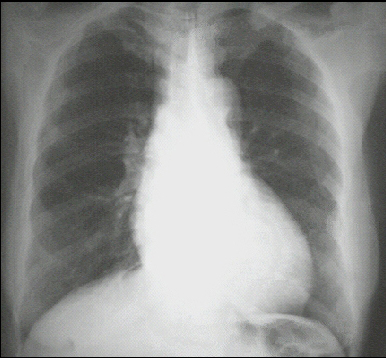

You are incorrect - the best interpretation of the chest X ray in our patient is pulmonary venous congestion.

This PA chest X ray is normal. It shows no abnormalities of the bone structures, lung fields or cardiac silhouette. The right and left heart borders are normal, as are the great vessels superior to the cardiac silouette. Note the cardiothoracic ratio is also normal.